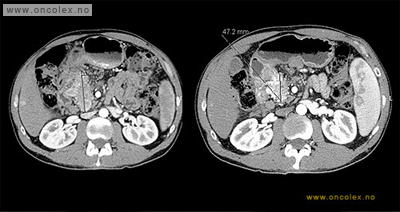

Bildeeksempler behandlingseffekt:

CT-bilder viser effekt etter to enkeltbehandlinger med 177-Lutetiumbehandling på hovedsvulsten i bukspyttkjertelen og en metastase til lever. Det er 4 måneder mellom bildene.